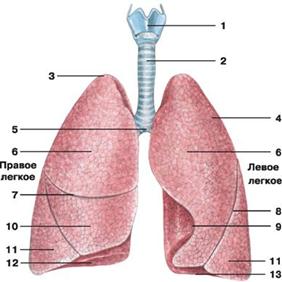

Рис. Легкие:

Рис. Легкие:

1 — гортань; 2 — трахея;

3 — верхушка легкого; 4 — реберная поверхность;

5 — раздвоение трахеи; 6 — верхняя доля легкого;

7 — горизонтальная щель правого легкого; 8 — косая щель;

9 — сердечная вырезка левого легкого; 10 — средняя доля легкого;

11 — нижняя доля легкого; 12 — диафрагмальная поверхность;

13 — основание легкого

Ацинусы (грозди) являются структурно-функциональными единицами легкого, которые осуществляют основную функцию легких - газообмен. В каждую легочную дольку входят 16-18 ацинусов. Ацинус начинается от концевой бронхиолы, которая дихотомически делится на дыхательные бронхиолы 1-2-3 порядка и переходит в альвеолярные ходы и альвеолярные мешочки с расположенными на их стенках альвеолами легких. Число легочных ацинусов в одном легком достигает 150000. В каждый ацинус входит большое количество альвеол.

Легкие (pulmones; гре. pneumones) - это парные дыхательные органы, представляющие собой полые мешки, подразделенные на тысячи обособленных мешочков (альвеол) с влажными стенками, снабженными густой сетью кровеносных капилляров. Легкие расположены в герметически замкнутой грудной полости и отделены друг от друга средостением, в состав которого входят сердце, крупные сосуды (аорта, верхняя полая вена), пищевод и другие органы. По форме легкое напоминает неправильный конус с основанием обращенным к диафрагме, и верхушкой, выступающей на 2-3 см над ключицей в области шеи. На каждом легком различают 3 поверхности: диафрагмальную, реберную и медиальную и два края: передний и нижний. Реберная и диафрагмальная поверхности отделены друг от друга острым нижним краем и прилежат соответственно к ребрам, межреберным мышцам и куполу диафрагмы. Медиальная поверхность, обращенная к средостению, отделяется от реберной передним краем легкого. На медиальной (средостенной) поверхности обоих легких располагаются ворота легкого, через которые проходят главные бронхи, сосуды и нервы, составляющие корень легкого.

Каждое легкое посредством борозд делится на доли. В правом легком имеется 3 доли: верхняя, средняя и нижняя, в левом - 2 доли: верхняя и нижняя. Доли разделяются на сегменты, которых в каждом легком примерно по 10. Сегменты состоят из долек, а дольки - из ацинусов.